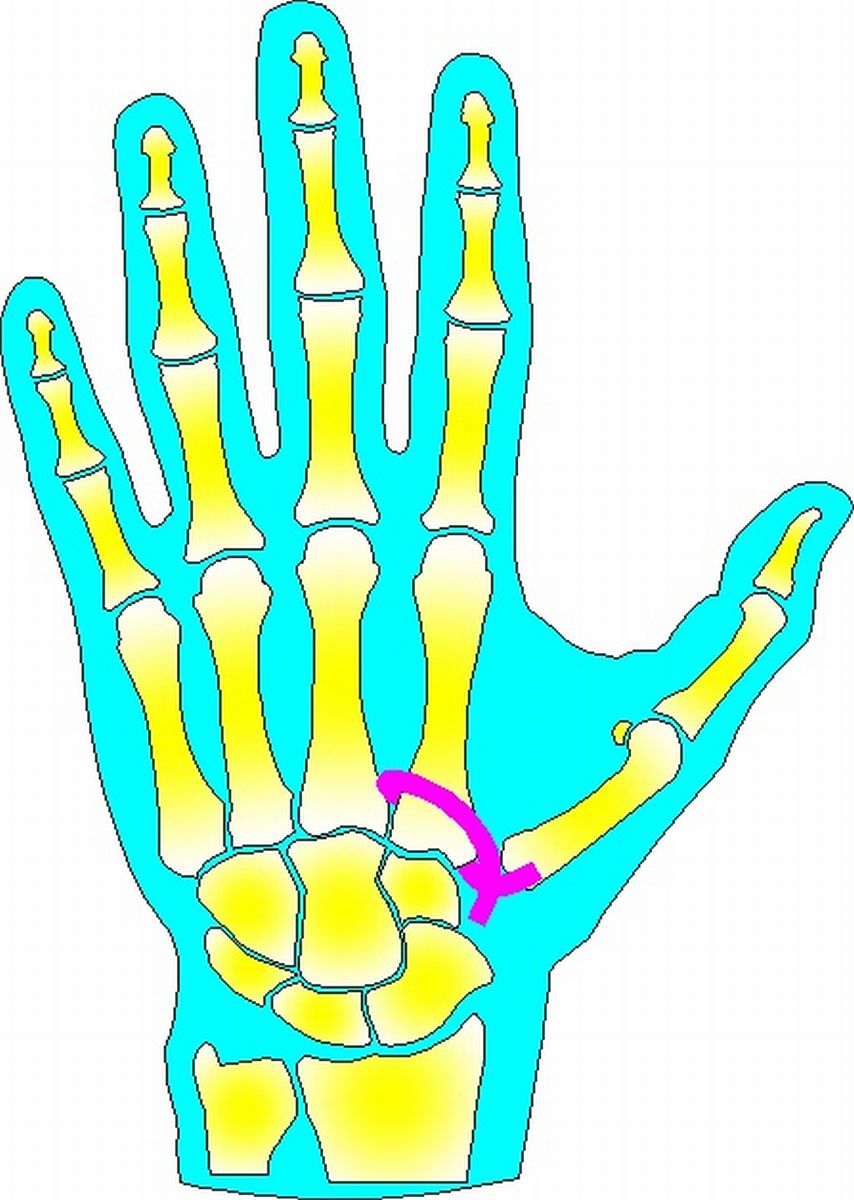

| Summary: after

trapeziectomy, a slip of abductor pollicis longus tendon is passed

around the base of the index metacarpal and sutured to itself proximal to the metacarpal base. |

| In this case, a vena cava

ligature passer was modified to create the path around the index

metacarpal base. |